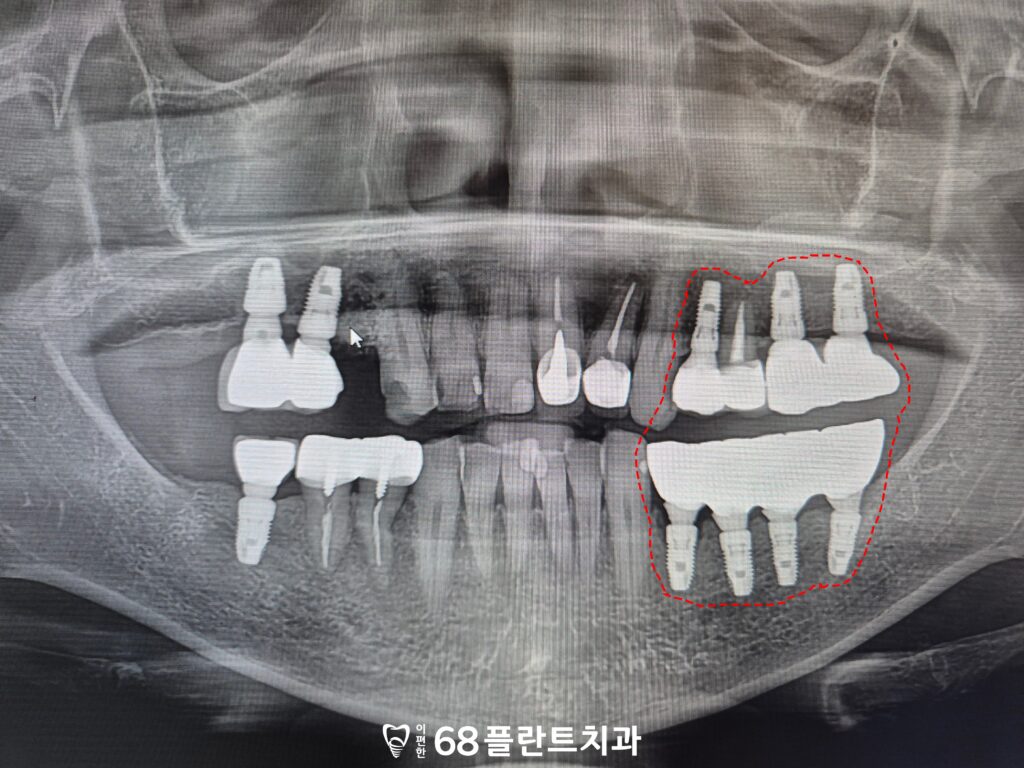

이후 아래쪽 치아를 발치하고

위쪽과 같이 임플란트를

식립하였습니다.

식립된 임플란트는 초기 안정성이

중요하기 때문에, 뼈와 잘 유착될 수 있도록

일정 기간은 과도한 저작이나

딱딱한 음식 섭취를 피해야 하고

철저한 구강 위생 관리가

필요한 점을 설명드렸습니다.

치유 과정이 순조롭게 마무리된 후,

본격적인 보철 작업을 시작하였습니다.

잇몸에 맞는 맞춤형 지대주를

제작하여 장착하였으며,

그 위에 최종 보철물을 완성했습니다.